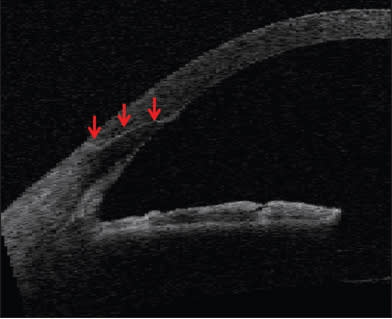

A clear-corneal incision made with a femto laser is indicated at the red arrows. IMAGE COURTESY OF WILLIAM CULBERTSON, MD.